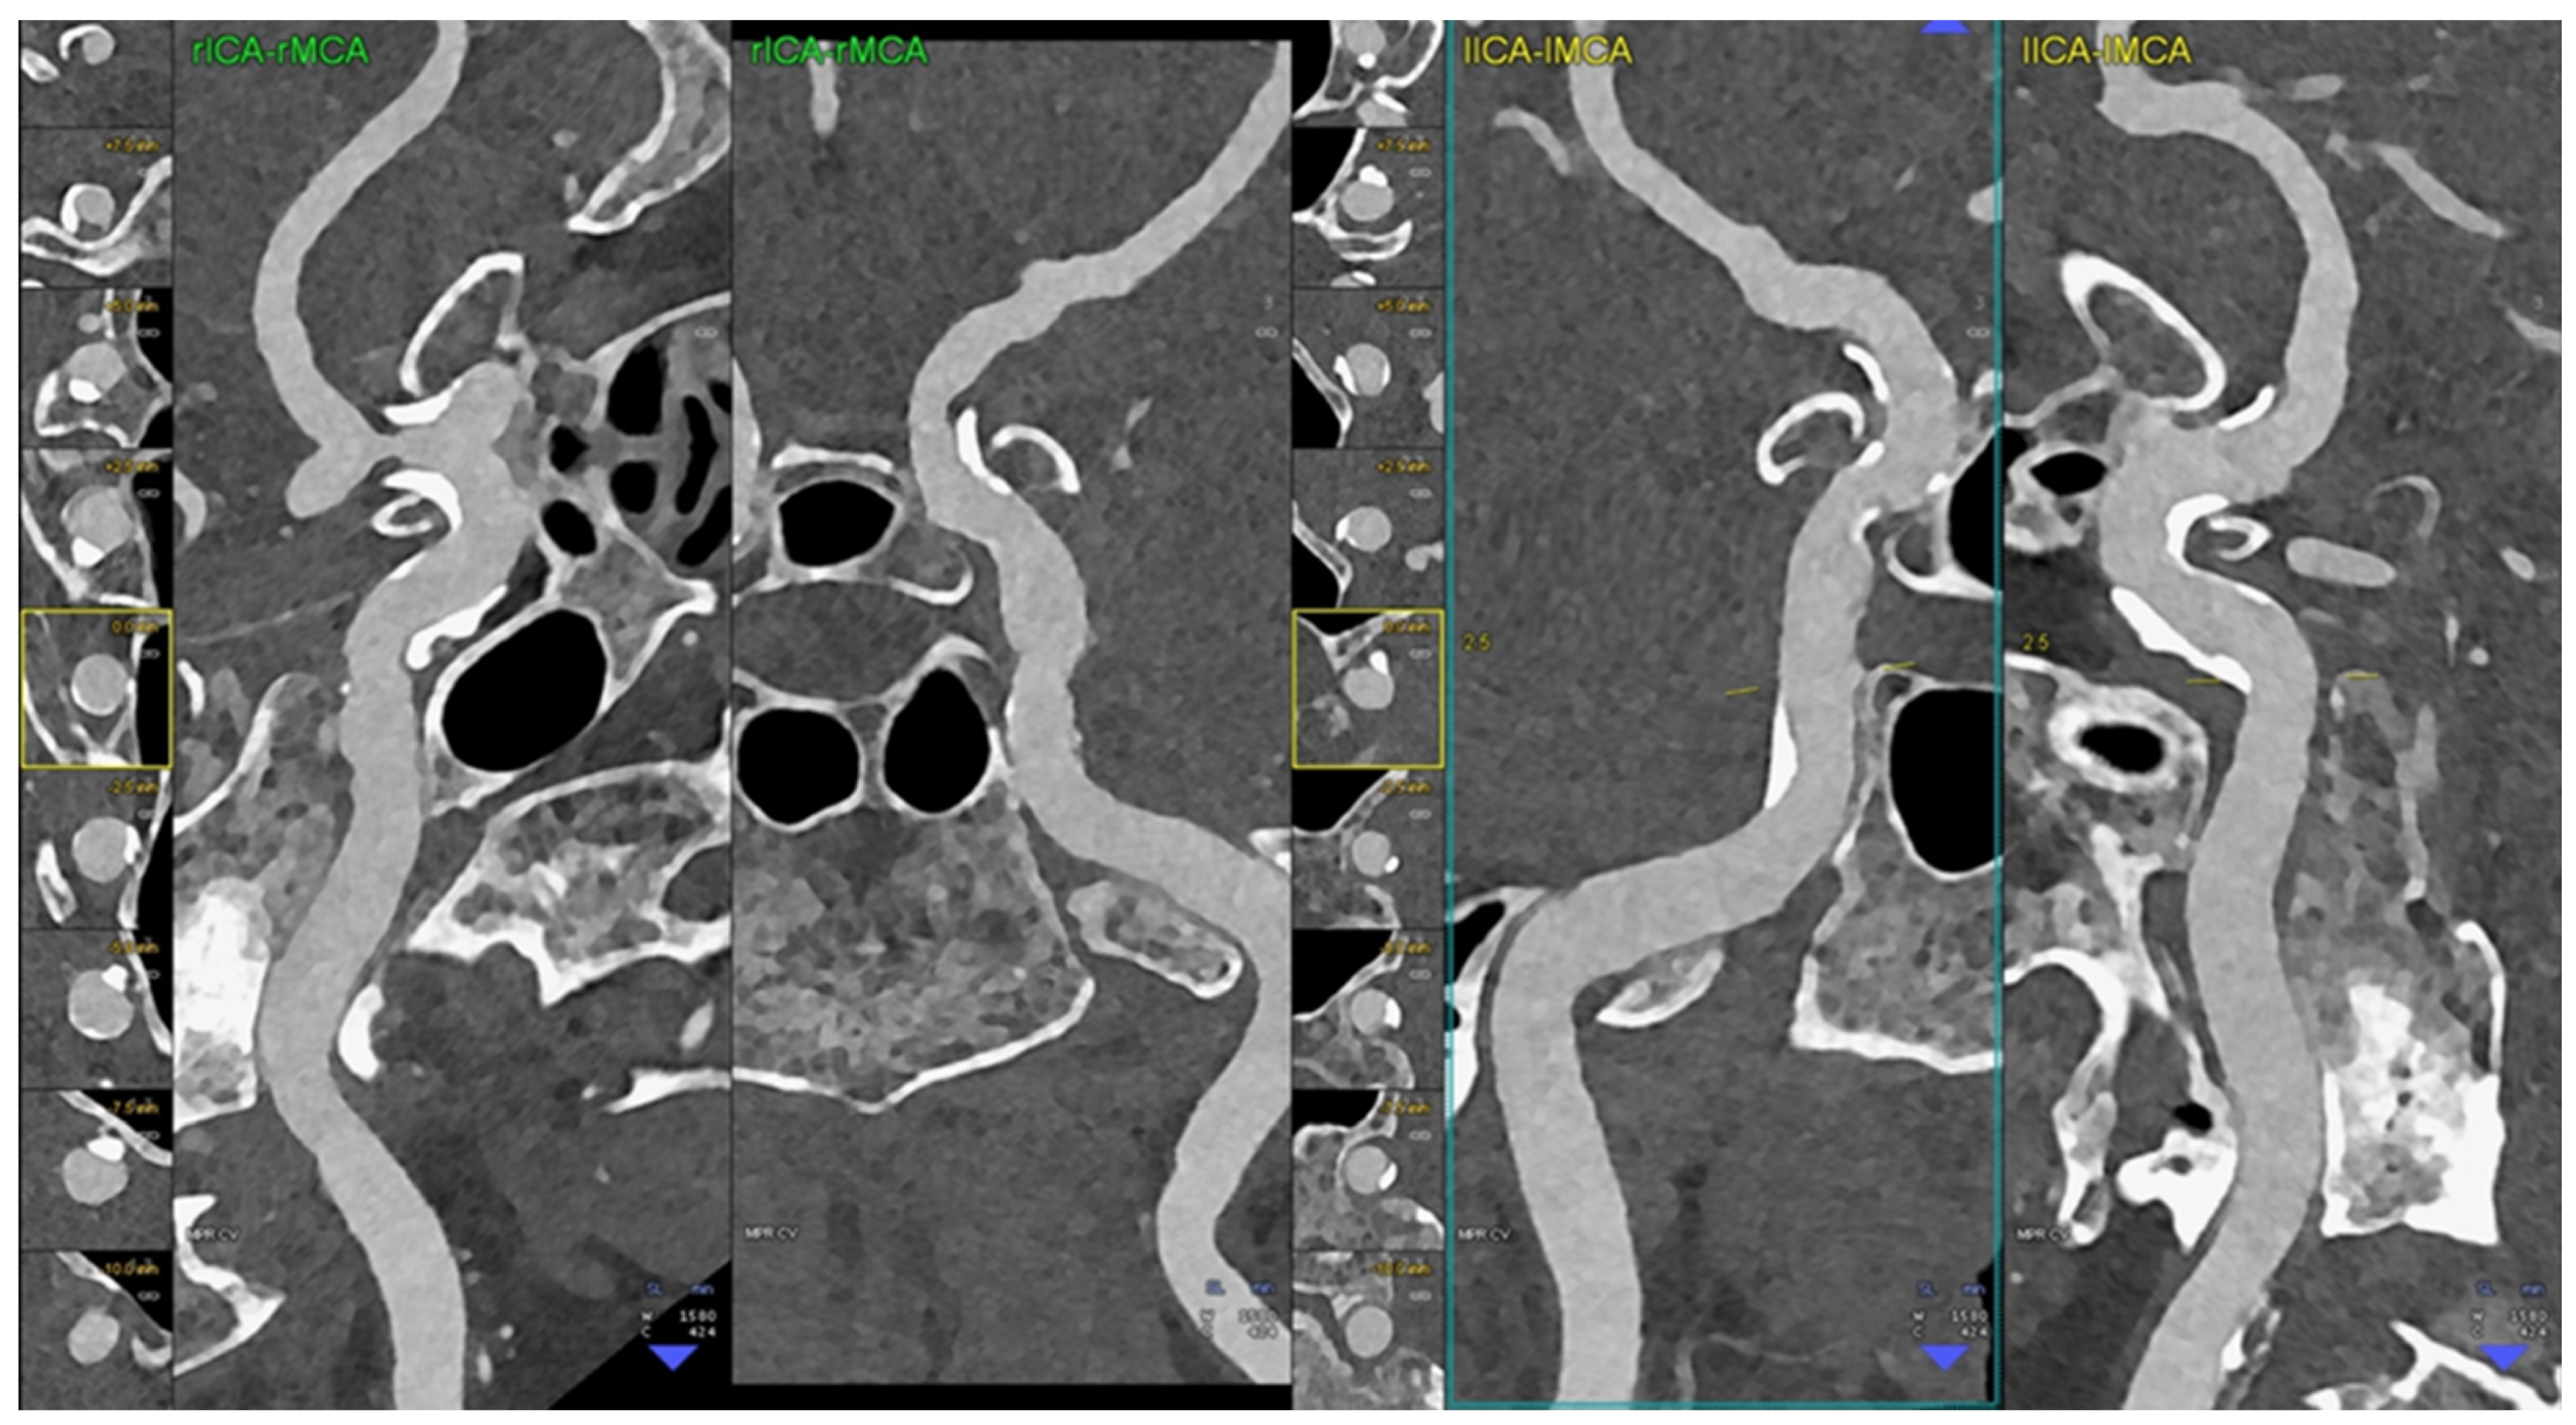

- Michael, A.E.; Boriesosdick, J.; Schoenbeck, D.; Lopez-Schmidt, I.; Kroeger, J.R.; Moenninghoff, C.; Horstmeier, S.; Pennig, L.; Borggrefe, J.; Niehoff, J.H. Photon Counting CT Angiography of the Head and Neck: Image Quality Assessment of Polyenergetic and Virtual Monoenergetic Reconstructions. Diagnostics 2022, 12, 1306. [Google Scholar] [CrossRef]